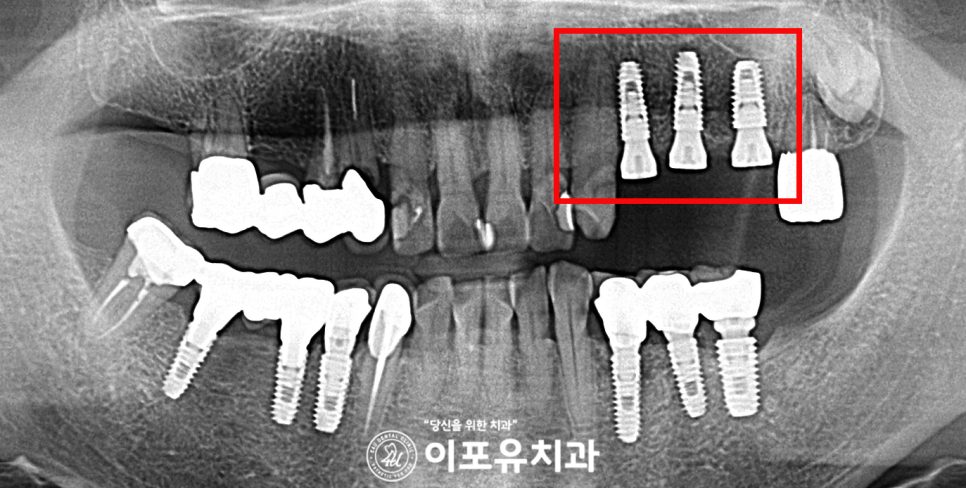

앞서 설명한 모든 식립을 마친 사진 입니다.

임플란트도 안정적으로 심어졌고

걱정했던 초기고정 부분에서도

예후가 좋을 거 같은데요.

보철도 자연치와

유사한 색상, 강한 경도를 위해

지르코니아로 제작하는 것이 좋습니다.